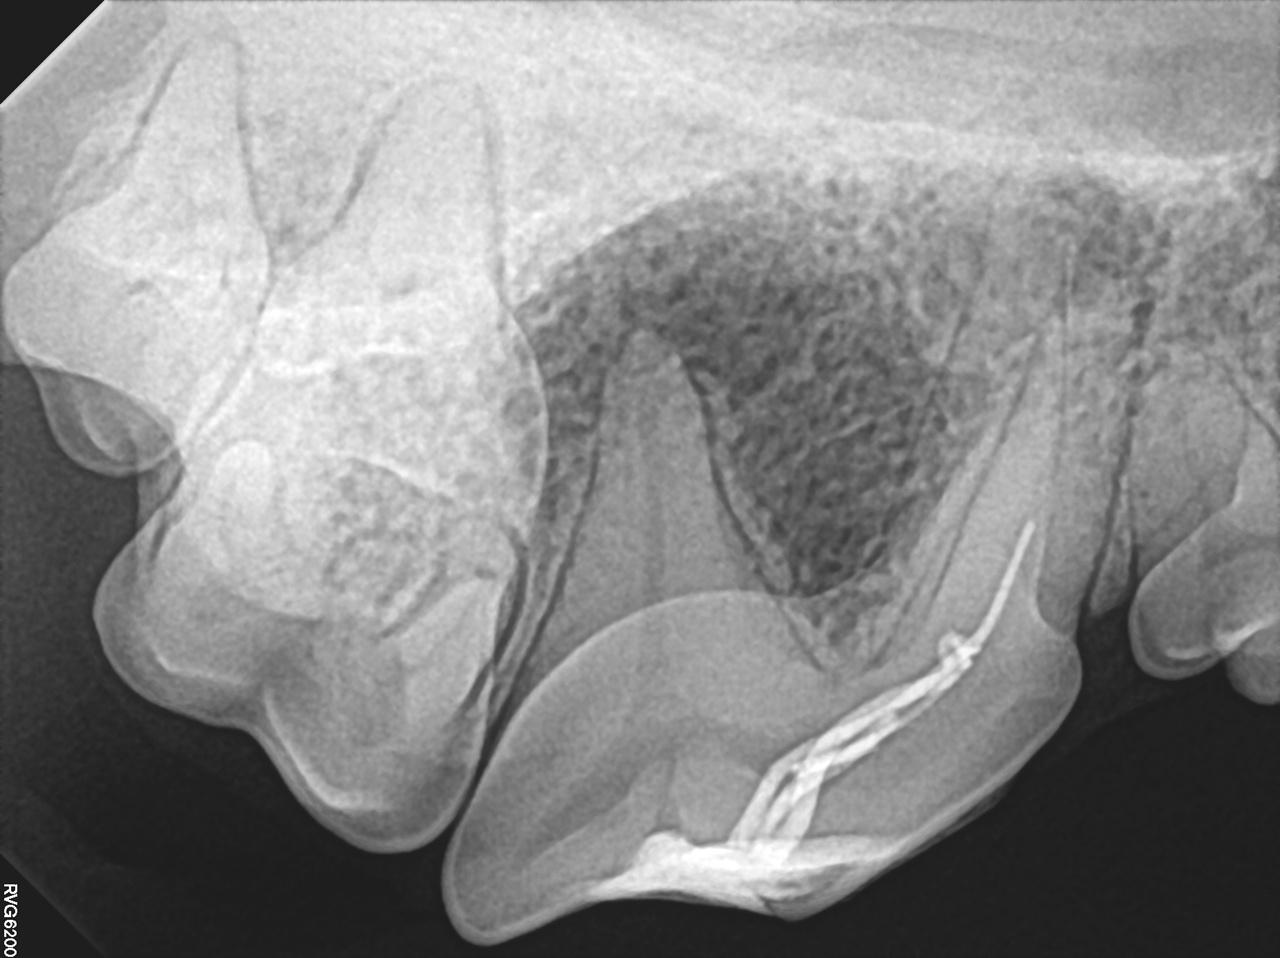

현재 수의치과학에서의 근관치료는 사람의 근관치료를 위해 개발되고 발전해 온 기구와 재료를 사용할 수밖에 없는 현실에 놓여 있다. 그러나 사람과 개, 고양이의 근관 해부학적 특성은 분명히 다르다. 따라서 이러한 기구와 재료를 개와 고양이의 근관 해부학에 맞게 적절히 변형(modification)하여 적용하는 것이 중요하다. 특히 사람에 비해 훨씬 복잡한 apical delta가 발달한 개와 고양이에서는 근단 1/3 부위를 얼마나 효과적으로 성형·세정·충전하는지가 높은 성공률을 좌우한다는 점이 최근 발표된 여러 문헌을 통해 확인되고 있다.